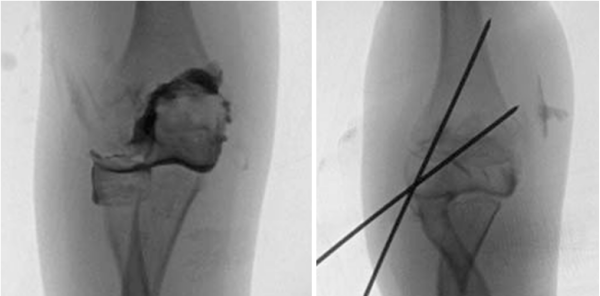

手术治疗-闭合复位内固定

闭合复位经皮固定:适用于2-4mm移位,全麻下通过屈肘、前臂旋前、外髁直接加压复位,用1.6mm克氏针固定,理想为2-3根成角>60°的克氏针,实现双皮质固定,残留移位需<2mm。

适应症选择:适用于骨折移位>2mm,但关节面软骨铰链完整或无明显旋转的骨折(如Weiss II型、Song II-IV型)。

手术核心技巧:

复位:手法或细针撬拨,将移位骨块推回原位。

固定:经皮穿入2-3根克氏针,优选交叉固定以增强稳定性。

图16 使用克氏针作为杠杆以辅助复位,然后继续推进至肱骨小头,并交叉固定骨折断端。

确认:术中反复透视或关节造影,确保关节面解剖复位。

图17 关节造影证实关节面平整。